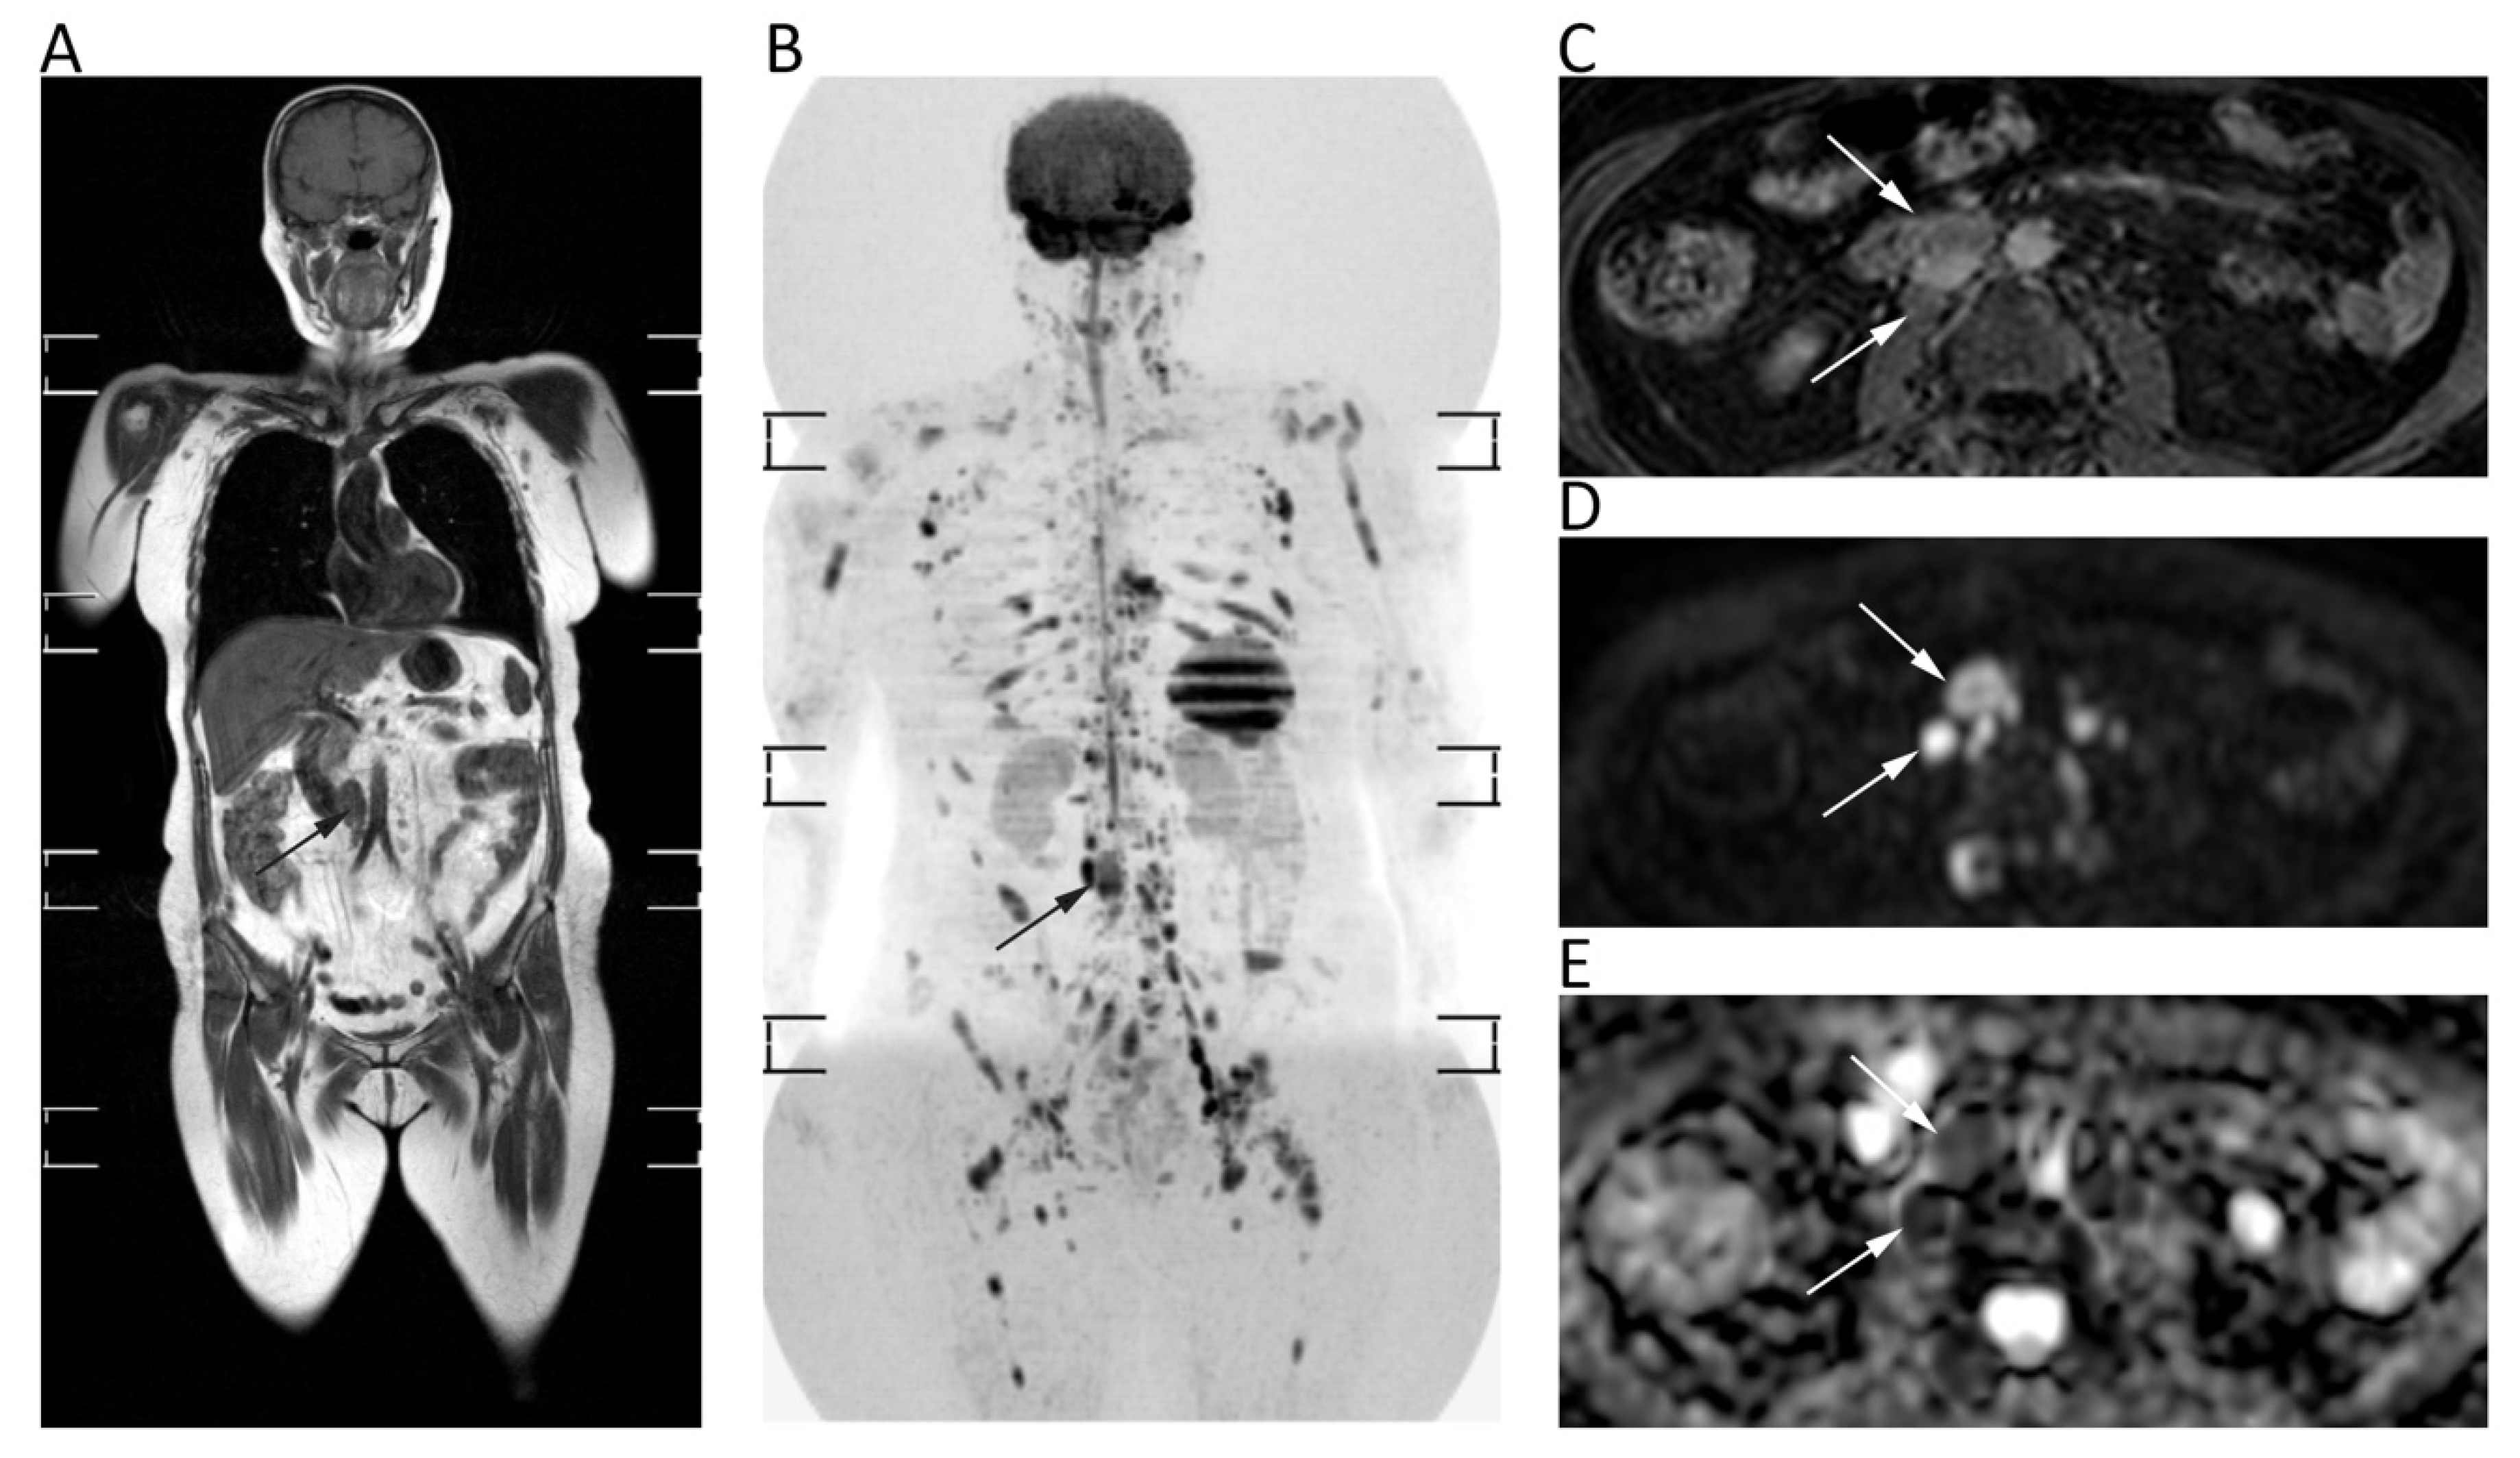

Whole-body (WB)-DWI-MRI has emerged as an accurate tool to stage lymphoma using DWI with background suppression (DWIBS). DWIBS is a single-shot echo-planar sequence characterized by signal acquisition with sensitivity encoding to improve resolution and decrease artefact at air interfaces, free breathing acquisition to increase signal to noise ratio, and homogeneous fat suppression by STIR technique [15]. DWI enables one to detect lymphomatous locations as lesions with very high signals on high-b-value images—generally higher signals than those of the spinal cord and muscles—and low ADCs due to the high cellularity and elevated nuclear-to-cytoplasm ratio of lymphoma [15]. Nevertheless, there is still no consensus on the b-values to be used on DWI sequences, although at least two b-values are applied with b = 1000 as the highest b-value image. The lack of consensus concerns also the best ADC cut-off to differentiate normal from lymphomatous lymph nodes, although several studies have shown that the latter often present mean ADC lower than 0.8 × 10−3 mm2/s (Figure 11) [86,87].

Figure 11.

Whole-body MRI of a 58-year-old female patient with non-Hodgkin lymphoma. Whole-body T1w (A) and coronal MIP grey-scale inverted DWI (B) show multiple nodal and bone locations of disease. Note the periaortic lymph nodal locations (arrows) with moderate contrast enhancement on axial fat-suppressed 3D GRE T1w (C) and restricted pattern of diffusion on axial b = 800 DWI (D) and corresponding ADC map (E, mean ADC: 0.761 × 10−3 mm2/s).

Moreover, it is not clear whether mean or minimum ADC should be used. In lymphoma staging, WB-DWI-MRI showed similar diagnostic performance to FDG-PET/CT with excellent agreement (k = 0.88) and high sensitivity (98%) and specificity (97%) for nodal involvement, presenting even higher accuracy than CT for both nodal (accuracy of WB-DWI-MRI and CT: 95.5% and 94.3%) and extra-nodal disease (accuracy of WB-DWI-MRI and CT: 98.5% and 76.3%) [87,88]. Despite the promising results of the above-mentioned studies, there is still no clinical application of ADC measurements for lymphoma.

In addition to its proven accuracy in lymphoma staging, WB-DWI-MRI has shown promising results to assess response after treatment. In most studies a qualitative evaluation of DWI and ADC maps has been used to evaluate treatment response with excellent results (94.7% sensitivity, 99.3% specificity). However, there is no enough evidence to introduce quantitative evaluation of treatment response by DWI in clinical practice, with only one study having proposed a mean ADC cut-off of 1.2 × 10−3 mm2/s to differentiate responding from non-responding lesions [89].